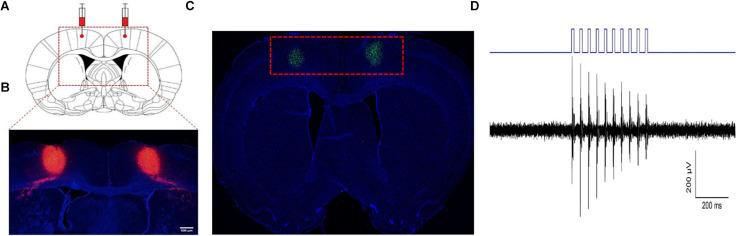

Although spinal cord injury (SCI) is the main cause of disability worldwide, there is still no definite and effective treatment method for this condition. Our previous clinical trials confirmed that the increased excitability of the motor cortex was related to the functional prognosis of patients with SCI. However, it remains unclear which cell types in the motor cortex lead to the later functional recovery. Herein, we applied optogenetic technology to selectively activate glutamate neurons in the primary motor cortex and explore whether activation of glutamate neurons in the primary motor cortex can promote functional recovery after SCI in rats and the preliminary neural mechanisms involved. Our results showed that the activation of glutamate neurons in the motor cortex could significantly improve the motor function scores in rats, effectively shorten the incubation period of motor evoked potentials and increase motor potentials' amplitude. In addition, hematoxylin-eosin staining and nerve fiber staining at the injured site showed that accurate activation of the primary motor cortex could effectively promote tissue recovery and neurofilament growth (GAP-43, NF) at the injured site of the spinal cord, while the content of some growth-related proteins (BDNF, NGF) at the injured site increased. These results suggested that selective activation of glutamate neurons in the primary motor cortex can promote functional recovery after SCI and may be of great significance for understanding the neural cell mechanism underlying functional recovery induced by motor cortex stimulation.

尽管脊髓损伤(SCI)是全球致残的主要原因,但对于这种病症仍没有明确有效的治疗方法。我们之前的临床试验证实,运动皮层兴奋性增加与SCI患者的功能预后相关。然而,运动皮层中哪些细胞类型导致后期功能恢复仍不清楚。在此,我们应用光遗传学技术选择性激活初级运动皮层中的谷氨酸能神经元,探讨初级运动皮层中谷氨酸能神经元的激活是否能促进大鼠SCI后的功能恢复以及涉及的初步神经机制。我们的结果表明,运动皮层中谷氨酸能神经元的激活可显著提高大鼠的运动功能评分,有效缩短运动诱发电位的潜伏期并增加运动电位的幅度。此外,损伤部位的苏木精-伊红染色和神经纤维染色显示,精确激活初级运动皮层可有效促进脊髓损伤部位的组织恢复和神经丝生长(GAP-43、NF),同时损伤部位一些生长相关蛋白(BDNF、NGF)的含量增加。这些结果表明,选择性激活初级运动皮层中的谷氨酸能神经元可促进SCI后的功能恢复,可能对理解运动皮层刺激诱导功能恢复的神经细胞机制具有重要意义。